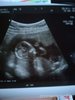

A to mój bobas

Śliczności [emoji7] Ale te nasze bobasy się zmieniają szybko :) dopiero były maleńkimi groszkami :)